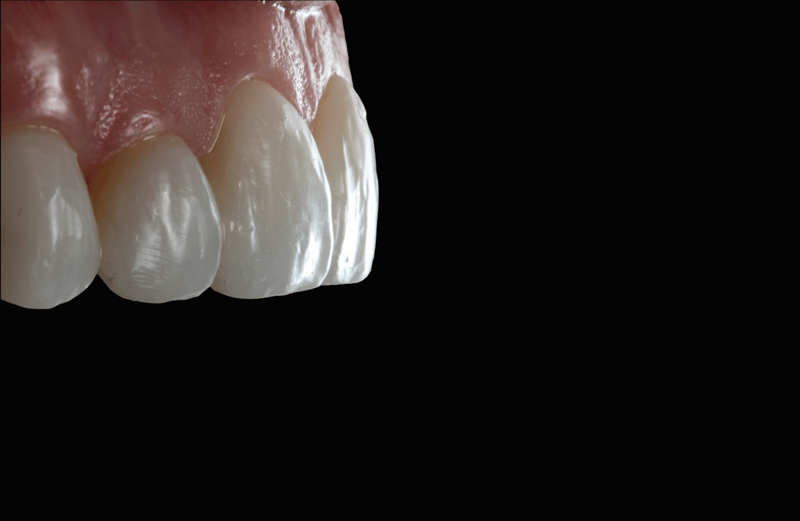

- Faciale anatomie: Voor het creëren van de faciale anatomie werd gebruikgemaakt van bolvormige en lange, dunne diamantboren. Met een gelobde diamantboor werden de lijnen van Retzius aangebracht. De eerste polijstbewerking werd gedaan met Jiffy™ Natural-polijstinstrumenten. De definitieve glans werd bereikt met Ultradent™ Diamond Polish Mint en de Jiffy™ Goat Hair Brush (niet beschikbaar in Europa), om de tertiaire anatomie niet te verwijderen.

Resultaat en beschouwing

Met de ingreep konden de esthetische problemen van de patiënte met succes worden aangepakt; de verkleuring van de frontelementen in de bovenkaak is gemaskeerd en er is nu sprake van een natuurlijk, evenwichtig beeld ten opzichte van de frontelementen in de onderkaak. Het gebruik van directe adhesieve composietveneers zonder preparatie bleek een conserverende, zeer effectieve oplossing te zijn die zowel tegemoetkwam aan de lastige financiële situatie van de patiënte als aan de behoefte aan een minimaal invasieve behandeling.